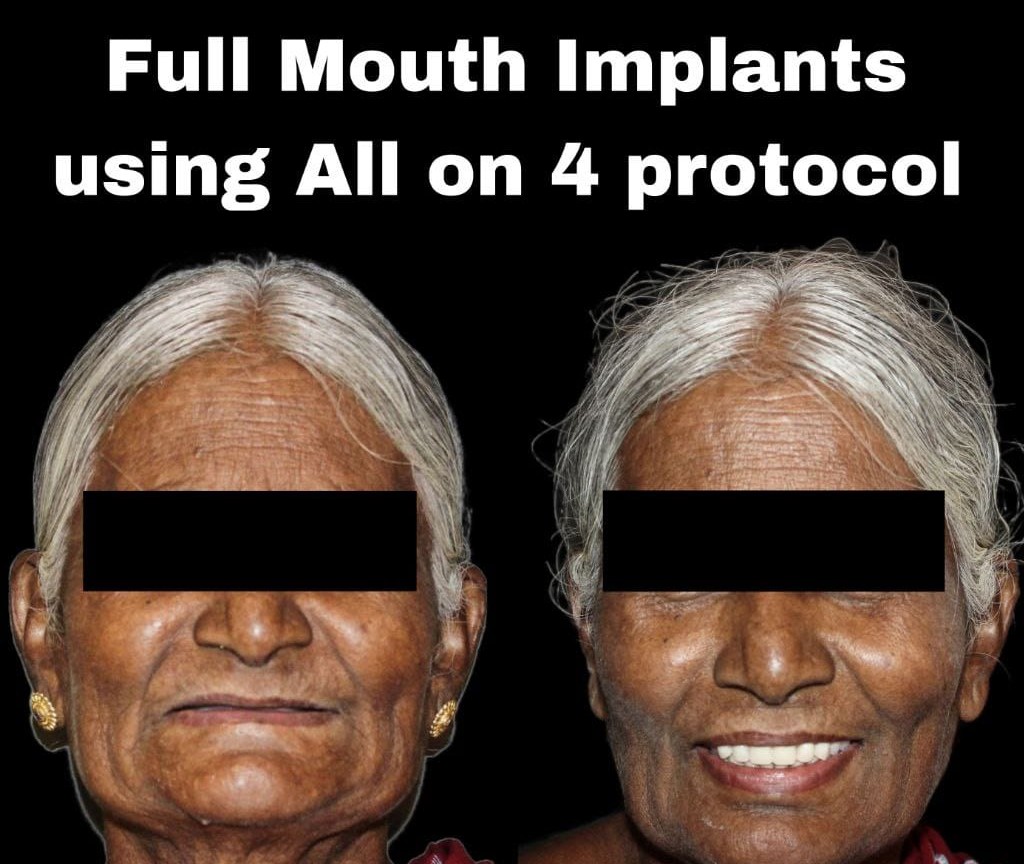

Expertise in Full Mouth Implants (All-on-4/6), Zygoma & Pterygoid implants, and Implant-supported prostheses.

A good Smile makes you feel ecstatic, invincible, playful, euphoric and on top of the World.

Full mouth rehabs optimize the health of the entire mouth, including the teeth, the gums, and the bite.

A comprehensive treatment plan that restores the function, health, and appearance of your entire mouth. It combines restorative and cosmetic dentistry to repair damaged teeth, correct bite issues, and enhance your smile.

Advanced implantology allows same-day teeth replacement or full-arch rehabilitation using the All-on-4 technique, providing quick and effective results.